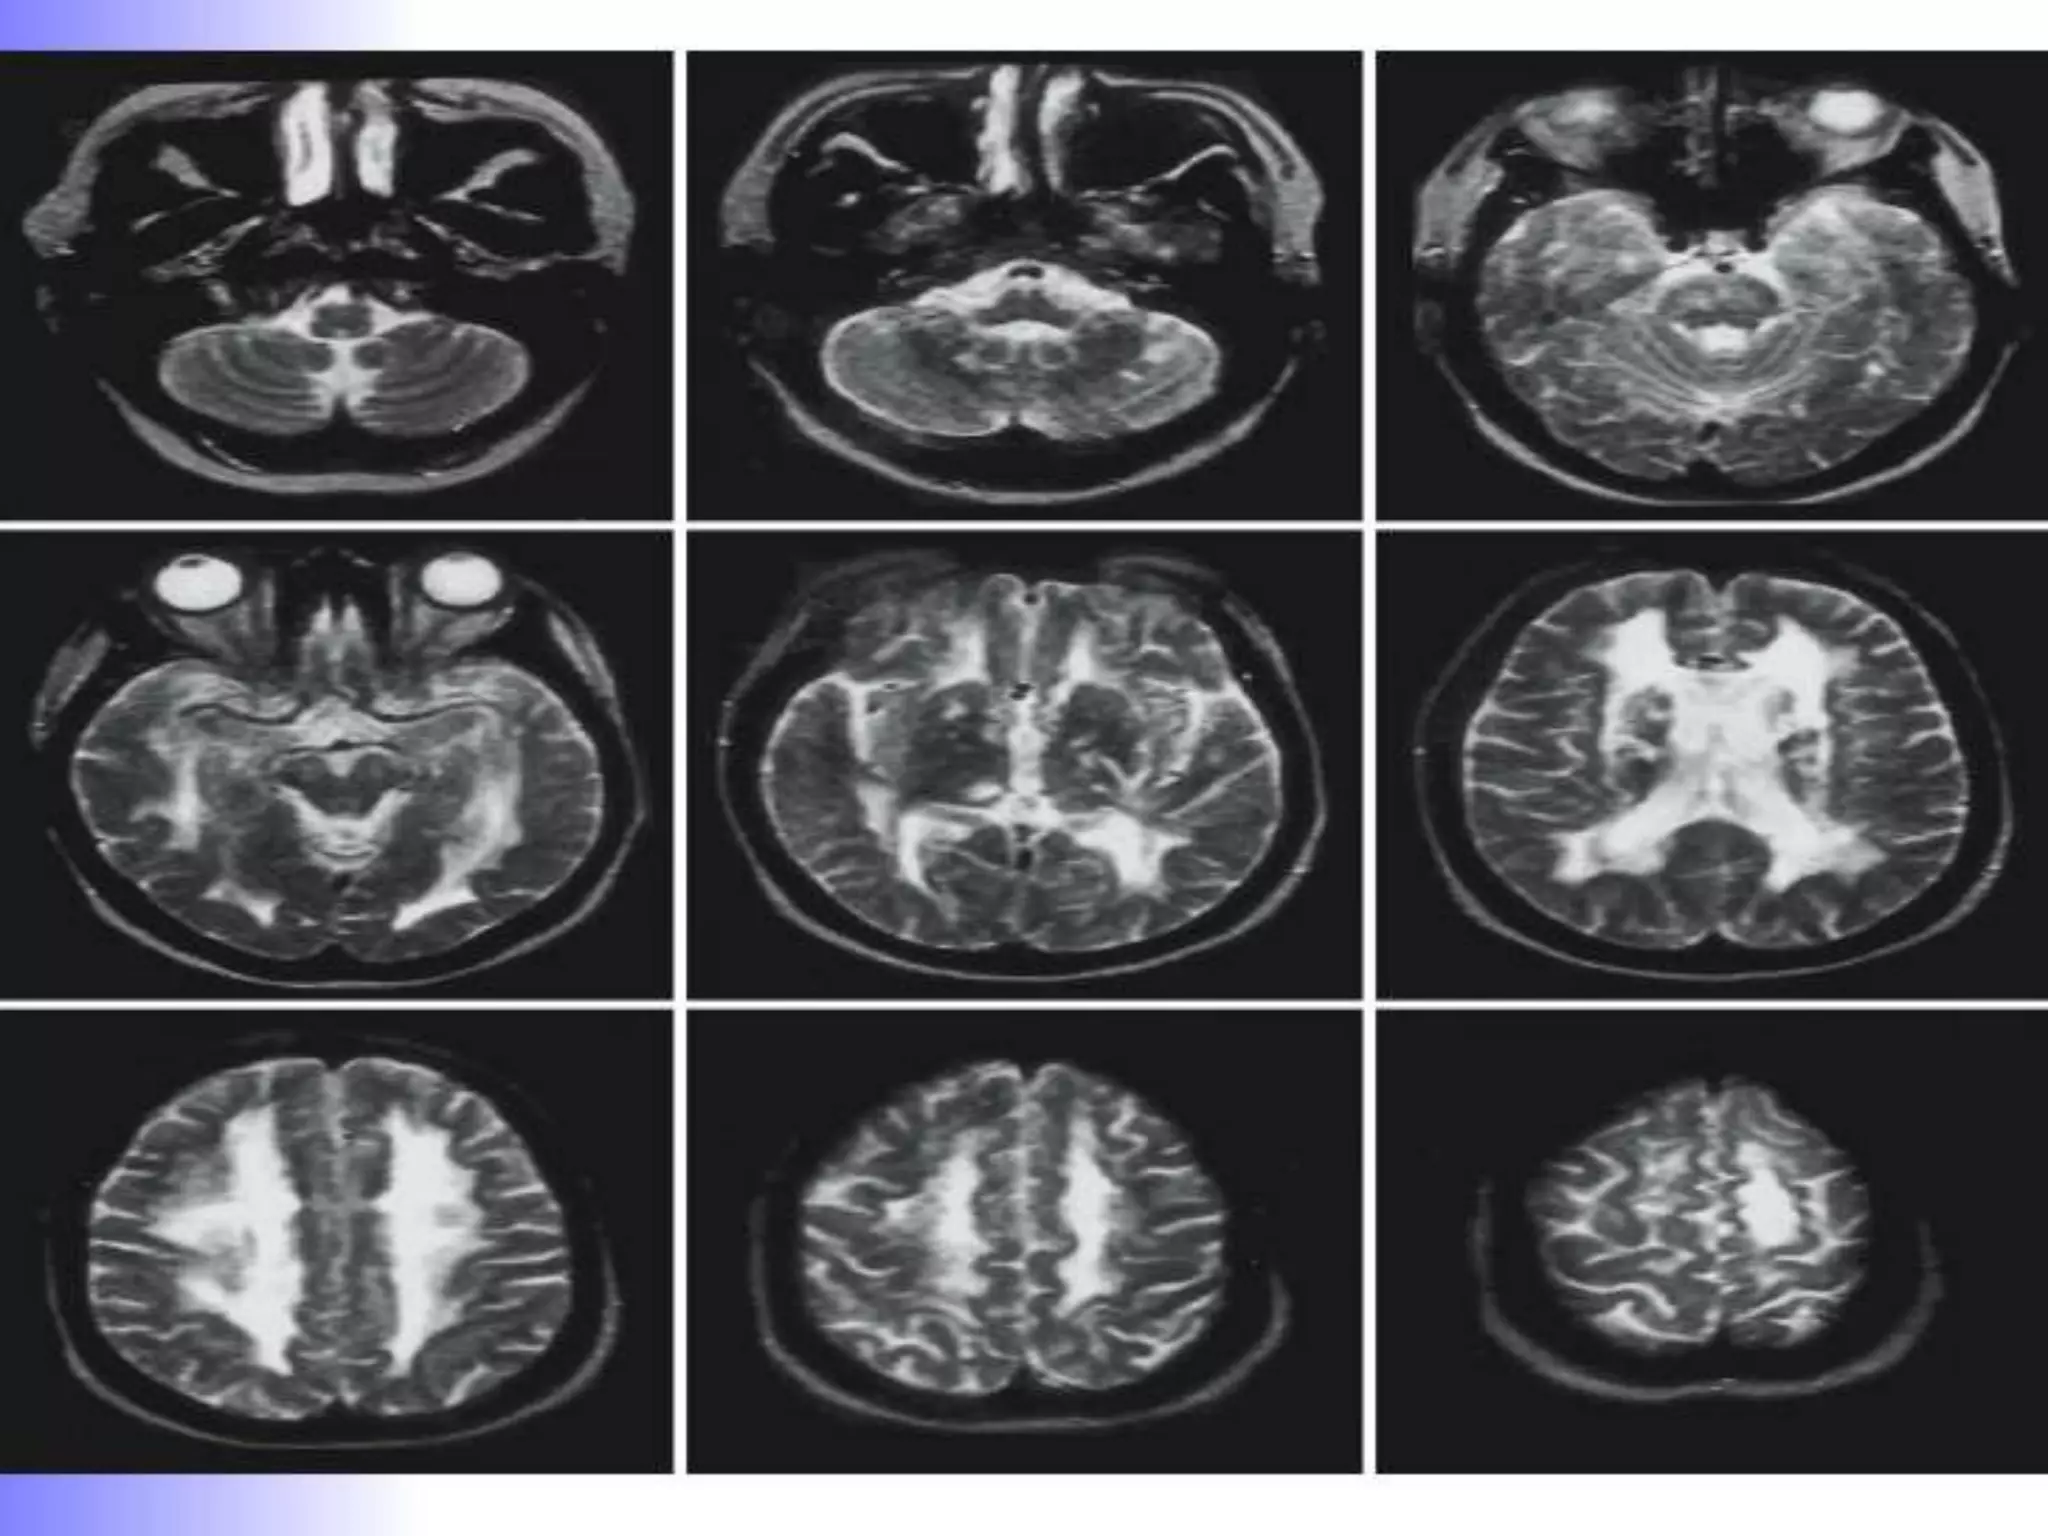

T2 Weighted MRI

Less distinct boundaries

between white and grey matter



Best for displaying pathology

Useful in demyelination, edema

& tumour infiltration

Gray matter medium gray

white matter dark grey

CSF and water White